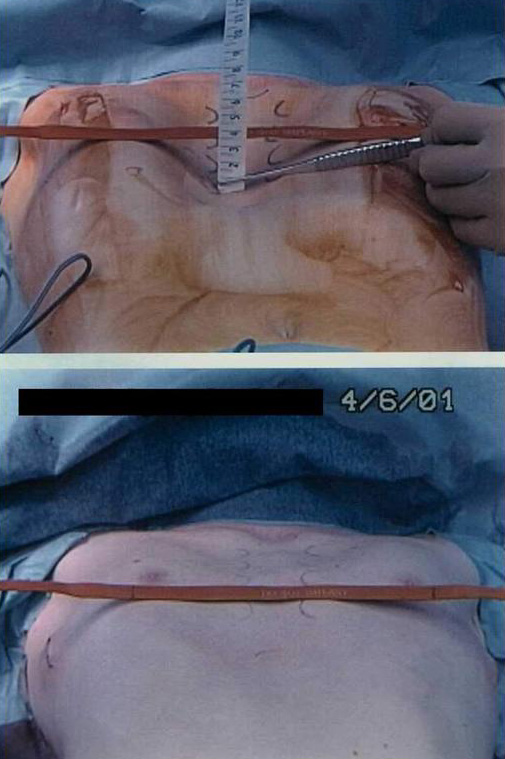

![]() |

| Figure 2. A sterile marking pen marks the skin at the interspaces of maximal pectus depth on each side of the sternum. In this example, the pectus depth measures 4.5 cm. |

Under general anesthesia, an epidural catheter is placed to aid in perioperative pain control. An endotracheal tube, radial arterial line, and Foley catheter are placed. A sterile marking pen marks the skin at the interspaces of maximal pectus depth on each side of the sternum. The defect usually involves the lower one half to two thirds of the sternum. The deepest point is typically just superior to the junction of the sternal body and the xiphoid process.

The preoperative anatomy is documented with photography in the AP plane (Figure 2) and lateral plane. Eventually, a retrosternal stainless steel bar will be placed from midaxillary line to midaxillary line at the level of maximal pectus depth. The length from midaxillary line to midaxillary line is measured in order to select the proper bar size.

The two incisions, each less than one inch long, are then closed with absorbable monofilament sutures (Figure 15). A chest X-ray is performed in the operating theater to document satisfactory bar position and evaluate for pneumothorax. The post-repair anatomy is documented with photography in the AP plane (Figure 16) and lateral plane. Patients are extubated in the operating theater.